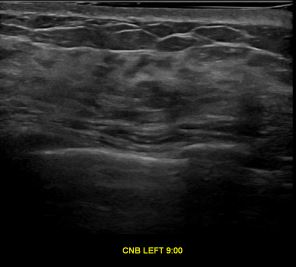

상기환자는 외부검사 이상소견으로 내원하신 40대후반 여성분으로 의심스러운 좌측혹

조직검사 시행해 제자리암으로 진단되었습니다